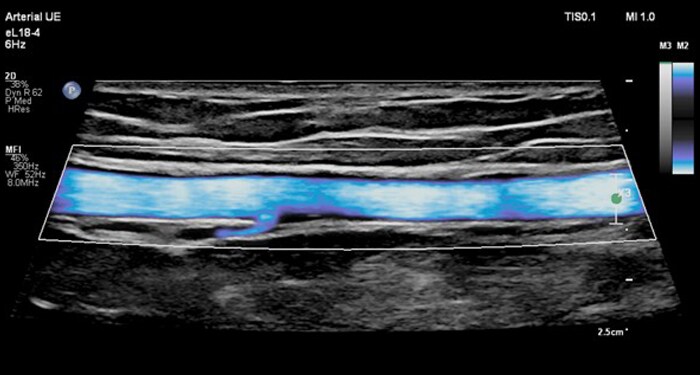

Vascular Imaging

The next level of vascular imaging

EPIQ Evolution 4.0

新しいeL18-4 PureWaveトランスジューサは、ウルトラブロードバンド PureWaveクリスタル(単結晶)テクノロジーと、圧電素子の多列配置による電子elevationフォーカシングにより、浅部から深部まで均一かつ高クオリティな画像を提供します。

MicroFlow Imaging

MicroFlow Imagingは、低流速の微細な血流を検出するために設計されたフィリップスの新しいモードです。